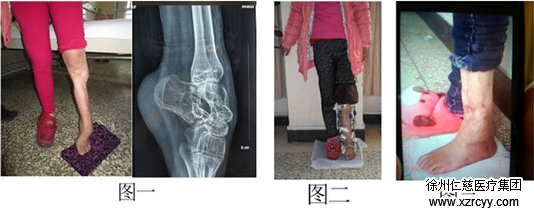

13岁的小红,因“左足外伤术后内翻畸形伴下肢短缩五年”入院。检查患者左小腿瘢痕挛缩,左踝关节僵硬,左足下垂内翻畸形,下肢短缩5cm(图一)。应用Ilizarov技术在胫骨截骨的基础上缓慢牵伸延长骨段,恢复肢体正常的长度,同时矫正足下垂(图二),是一期手术解决了两个不同的问题,节省病人的花费,取得满意的效果。患者拆除环形外固定架后肢体恢复长度和矫正马蹄足的体表情况(图三)。